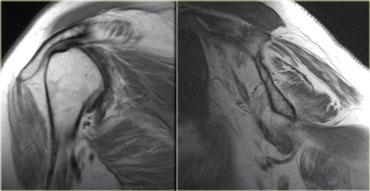

Cơ khuỷu trên ròng rọc phụ (mũi tên đỏ) – Thần kinh trụ tăng tín hiệu gợi ý viêm thần kinh trụ (mũi tên xanh)

Hình bên trái là hình ảnh khớp khuỷu, mặt trong nằm ở bên trái.

Lưu ý có một cơ nằm ngay phía sau thần kinh trụ, trong điều kiện bình thường cơ này không hiện diện tại vị trí này.

Đây là cơ khuỷu trên ròng rọc phụ (accessory anconeus epitrochlearis), gặp ở khoảng 10% dân số.

Đây là nguyên nhân thường gặp gây viêm thần kinh trụ do chèn ép, biểu hiện bằng đau và tê bì mặt trụ của bàn tay, đôi khi kèm teo cơ mô út và mô cái.

Cần quan sát kỹ thần kinh trụ khi phát hiện cơ phụ này.